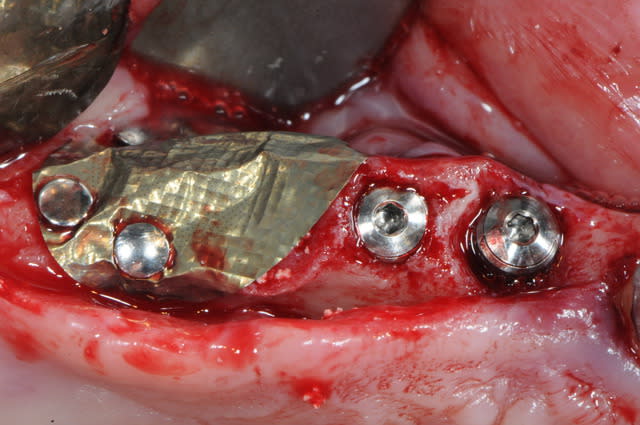

la tête est entièrement recouverte et sous la membrane je mets de l'os parcellaire ou du bio mat

je puis t'assurer que c'est de l'os sous la membrane quand on la retire. sinon, ça fait très longtemps que je ne l'utiliserai plus.

en ce qui concerne le nombre de clous; il semble qu'il y en ait beaucoup, mais la morphologie réelle de l'os et la difficulté à reconstruire un tel volume est difficilement visible avec des photos.